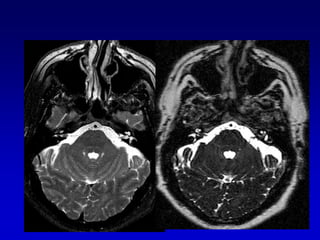

Lesión intracanalicularScreening con  T2 DRIVEExclusión con secuencias T1 Gd que son las secuencias mas sensibles para el Schwannoma intracanalicular, pero no siempre especificas, a veces es difícil la diferenciación con neuritis

Secuencias T2 (DRIVE)Secuencias T2 muy finas permiten información esencial y por lo tanto,  se usan de rutina . Ellas permiten la evaluación de  Tamaño del tumorErosión osea del CAI Neuritis vs ( nervio normal)  Schwannoma

Secuencias T2 (DRIVE)Con el T2 puede verse el LCR en el fondo de saco del CAI